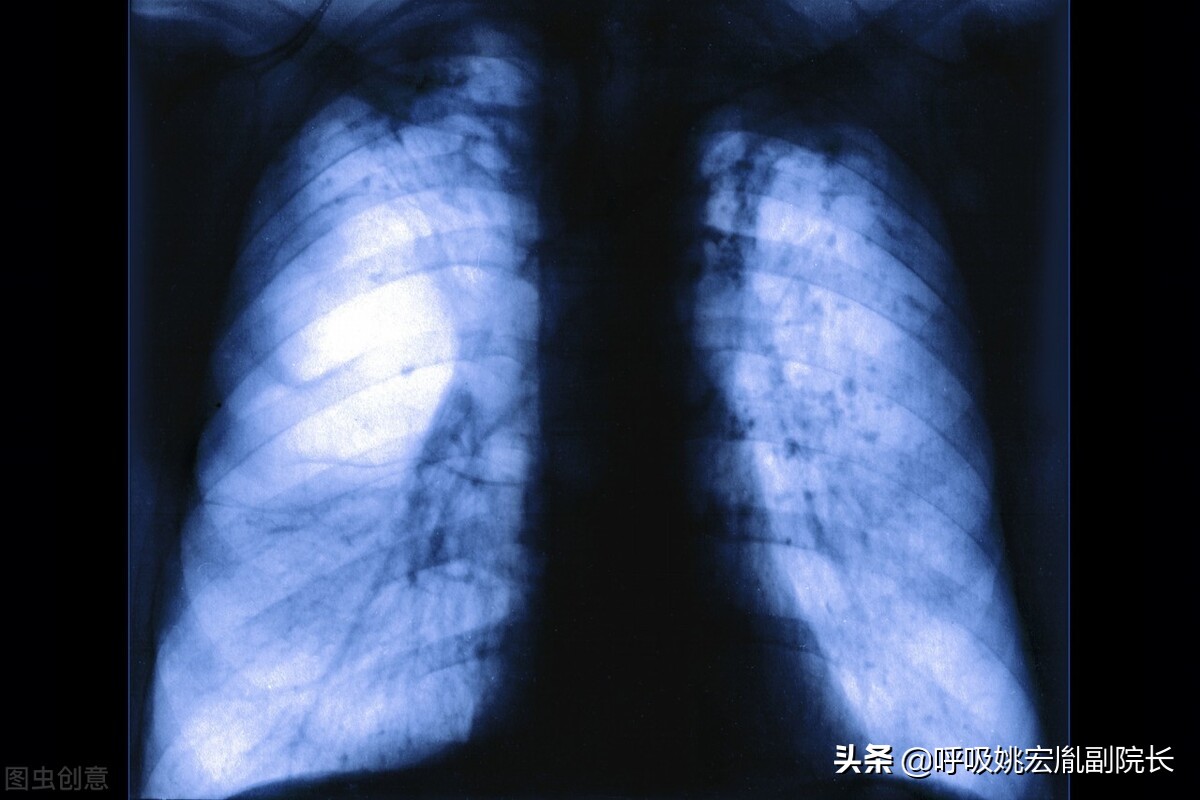

今天我们讲解一下生活中几种常见的肺病,这些疾病的症状表现有相同的症状,也有各自其独有的症状,今天我们来为肺病做一个基本的了解,让大家认识一下肺病。

常见的几种肺病:

肺炎:老年肺炎常缺乏明显呼吸系症状,症状多不典型,病情进展快,易发生漏诊、错诊。首发症状为呼吸急促及呼吸困难,或有意识障碍、嗜睡、脱水、食欲减退等。

肺气肿:肺气肿是指终末细支气管远端的气道弹性减退,过度膨胀、充气和肺容积增大或同时伴有气道壁破坏的病理状态。按其发病原因肺气肿有如下几种类型:老年性肺气肿、代偿性肺气肿、间质性肺气肿、灶性肺气肿、旁间隔性肺气肿、阻塞性肺气肿。

肺结节:肺结节是指在肺实质内而不属于正常肺策划的结节状阴影,直径小于3厘米,其中直径小于1厘米的称之为小结节,直径小于3毫米的称之为微结节,而大于3厘米的我们称之为肿块。肺结节可以表现为单独一个,也可以是多个。80%-90%以上的肺结节都是良性的,当然也有一部分结节是恶性的,而少数肺良性结节在随访的过程中可能会出现恶变。

慢阻肺:慢性阻塞性肺病简称慢阻肺,该病是由于一系列的因素(尤其是营养不良,是慢阻肺的“难兄难弟”)导致肺部感染,病情迁延不愈,最终导致慢阻肺,如果没听过慢阻肺,那你一定知道老慢支,慢阻肺就是老慢支的加强版。具有高发病率,高住院率,高死亡率的特点。